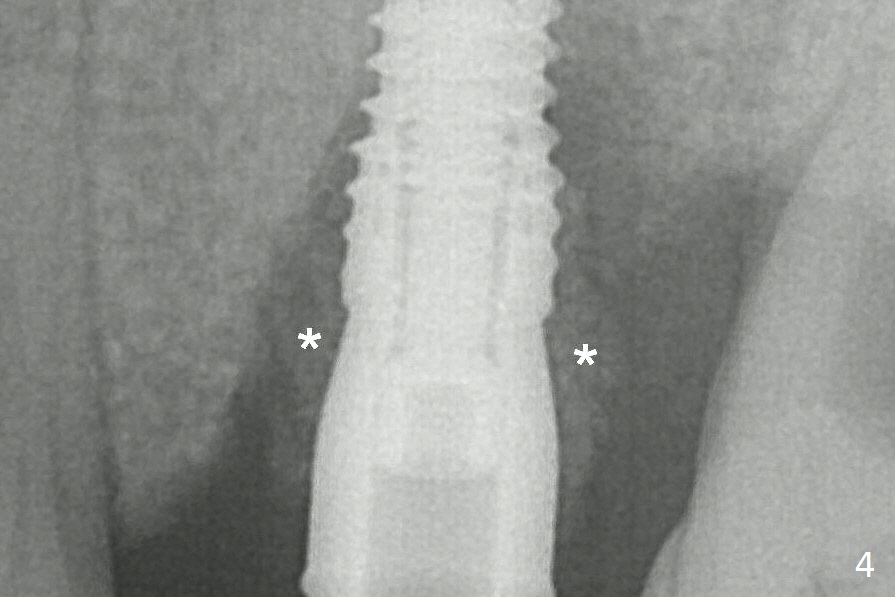

Bone Graft (Fig.4 *) is shown around the implant and a longer abutment (4.5x5.5(5) mm) after trimming. The graft cannot be pushed to the mesial surface of the tooth #14, probably due to the presence of the interdental papilla.